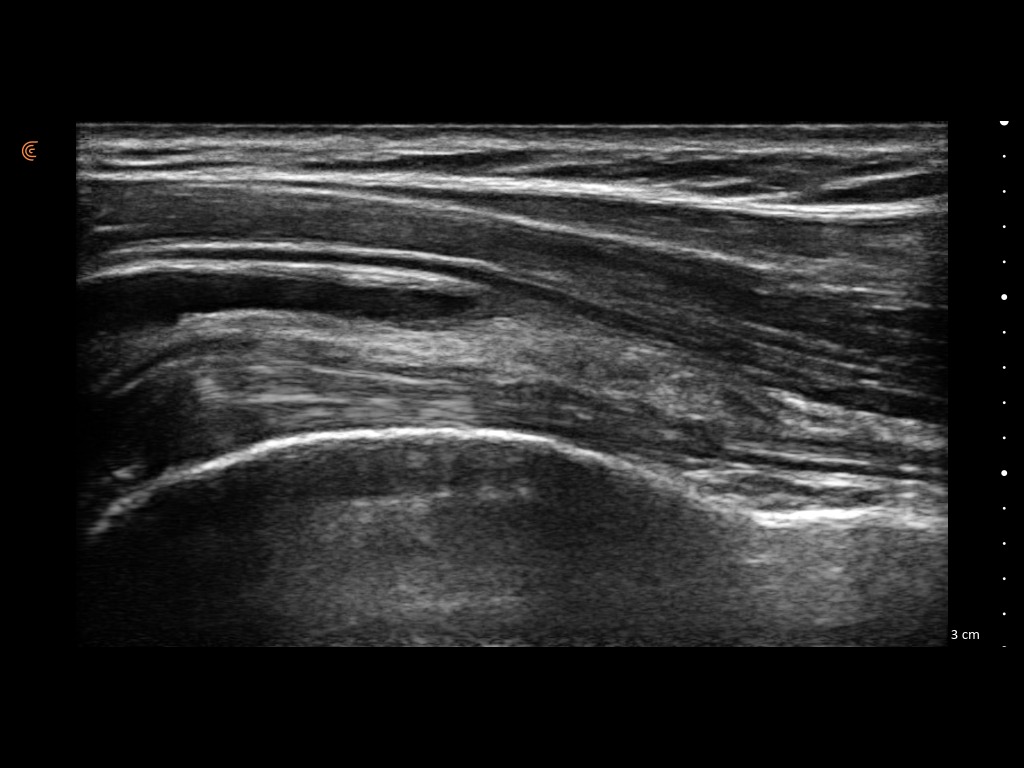

At TruMotion Therapy we are proud to offer our patients diagnostic ultrasound imaging services. Diagnostic ultrasound uses high frequency sound waves to create an image of the area being scanned. This allows Dr. Sankey to accurately diagnose musculoskeletal injuries providing or patients with certainty in their diagnosis and a treatment plan that will lead to them moving and feeling better.

Some common conditions that we have been able to diagnose with ultrasound and effectively treat include:

- Muscle strains: By identifying the severity of muscle strain we can help accurately gage the recovery timeline.

- Tendinitis vs Tendon Tear: Providing reassurance or encouraging caution is a benefit of visualizing the injured tissue.

- Bursitis: This condition is treated differently than normal muscle injuries. Knowing this information early is key.

- Nerve Entrapment: Knowing the site of nerve entrapment, like carpal tunnel syndrome, helps us direct a targeted treatment.